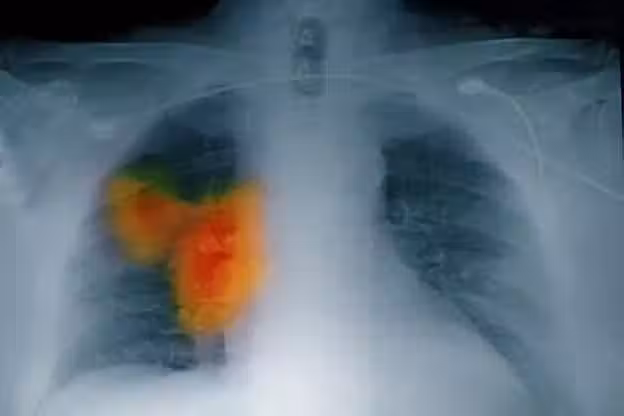

58歲女子確診肺癌,強忍淚水坦言:手部早出現了問題,沒有多重視

在這裡得跟大家說個關鍵的事兒,很多人都沒意識到,手部的一些小變化,就像藏在身體里的 「小警報」,可能和其他重要器官的疾病緊密相連。

比如說,手部要是一直麻麻的、沒力氣,或者時不時輕微地抖兩下,這很可能是神經系統或者血液循環系統出問題的信號。

在糖尿病、心臟病這些慢性病患者身上,這種情況就很常見。

而在李阿姨的身上,手部的這些問題,居然成了早期肺癌的一個危險信號。